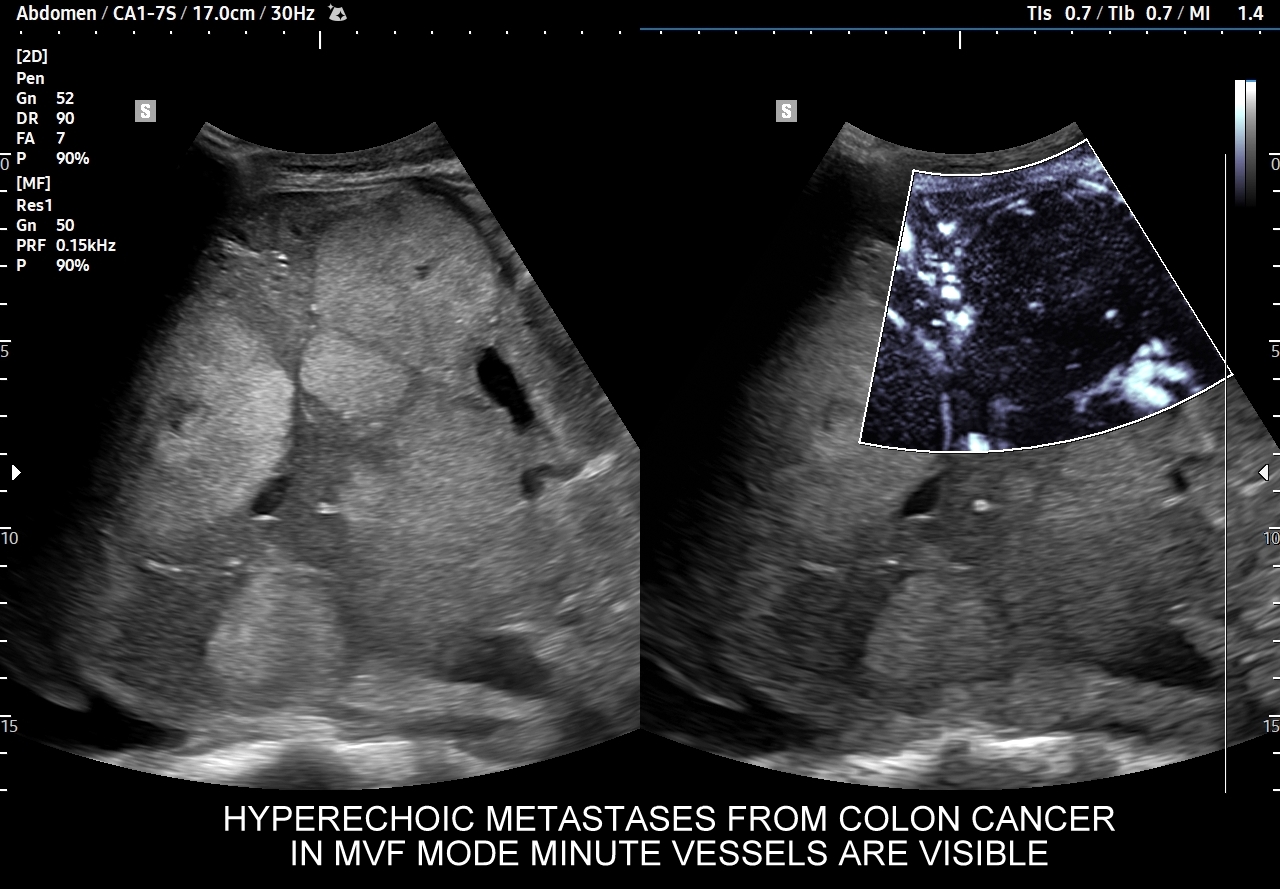

W badaniu USG w prezentacji B w niestłuszczonej wątrobie typowy naczyniak włośniczkowy lokalizuje się w pobliżu gałęzi żyły wątrobowej, a prezentuje się jako ostrookonturowana, hyperechogenna, jednorodna, krągła lub owalna zmiana ogniskowa. Ze względu na niską prędkość przepływu krwi i wynikające z tego ograniczenie detekcji w trybie color-Doppler w naczyniaku nie rejestruje się sygnału. Z kolei w trybie mikrounaczynienia (MVI / MVF) w zależności od czułości aparatury w naczyniaku można zaobserwować delikatny sygnał w postaci „poprószonego śniegu”.

W przypadku zarejestrowania w obrębie hyperechogennej zmiany ogniskowej wątroby w trybie kolorowego Dopplera lub Dopplera mocy (ang. power Doppler) drobnego naczynia lub naczyń, w szczególności krętych i o nieregularnym przebiegu, należy brać pod uwagę prawdopodobieństwo obecności złośliwej zmiany metastatycznej lub innego rodzaju zmiany ogniskowej.